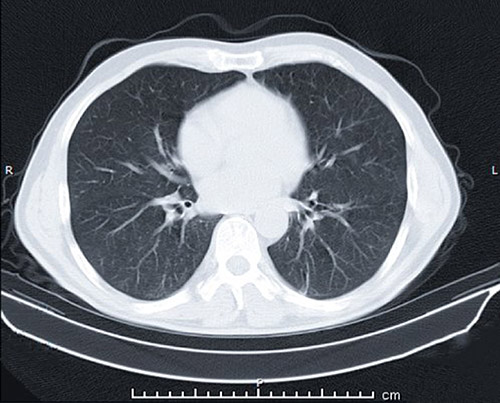

Self-reports of vaping THC directed providers to widen their differential diagnoses to include EVALI due to the connection between vaping products containing vitamin E acetate and the development of a systemic inflammatory response. Pneumonia was also considered, as well as appendicitis related to abdominal symptoms. While results from blood and urine analysis and imaging were negative, chest X-rays indicated mild opacities. The patients’ vaping history prompted a chest CT, which further revealed bilateral ground-glass opacities in all three patients leading to a diagnosis of EVALI. Treatment included methylprednisolone, ceftriaxone, and azithromycin. Patients were weaned off oxygen support and discharged home within two to three days with instructions to complete their full course of treatment and follow-up with a pediatric pulmonologist to confirm symptom resolution.

An example of a CT scan of the lung.